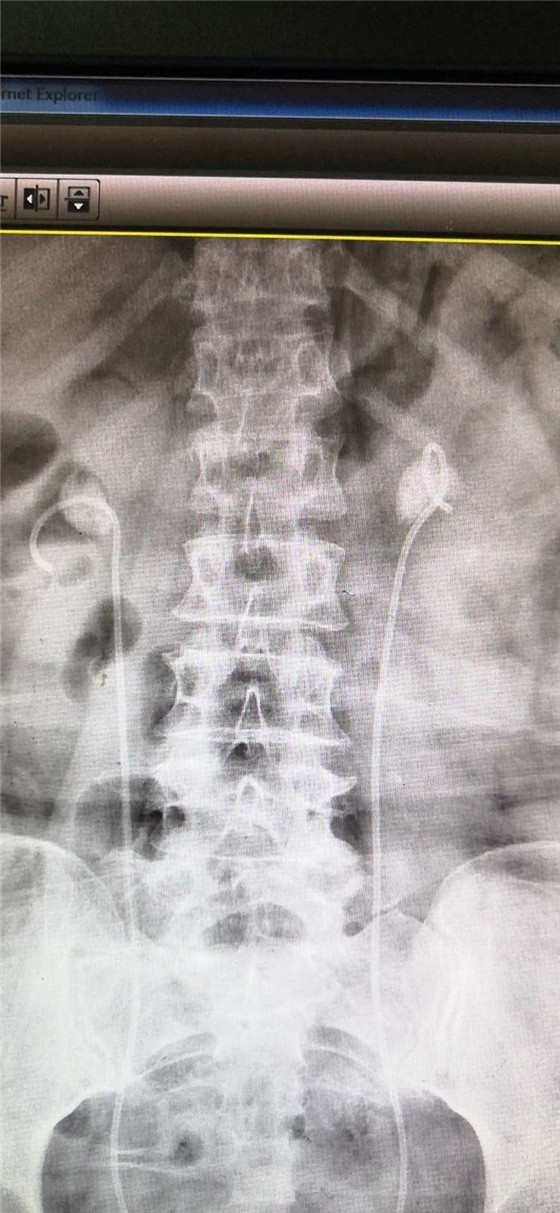

患者双肾结石,术前留置输尿管内支架管